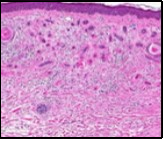

Lesions are generally superficial and infrequently invade lower dermis. Tendency for peri-neural or intra-neural infiltration, cogitated in adjunctive cutaneous carcinomas, is exceptional in desmoplastic trichoepithelioma. Nevertheless, desmoplastic trichoepithelioma can be exemplified as a component of particularly desmoplastic, cutaneous carcinomas demonstrating foci of peri-neural involvement 4, 5. Figure 1, Figure 2, Figure 3, Figure 4, Figure 5, Figure 6, Figure 7, Figure 8.

Figure 5.Desmoplastic trichoepithelioma enunciating several horn cysts, nests of basaloid cells, an enveloping desmoplastic stroma and thinned out superimposed epithelium 12.